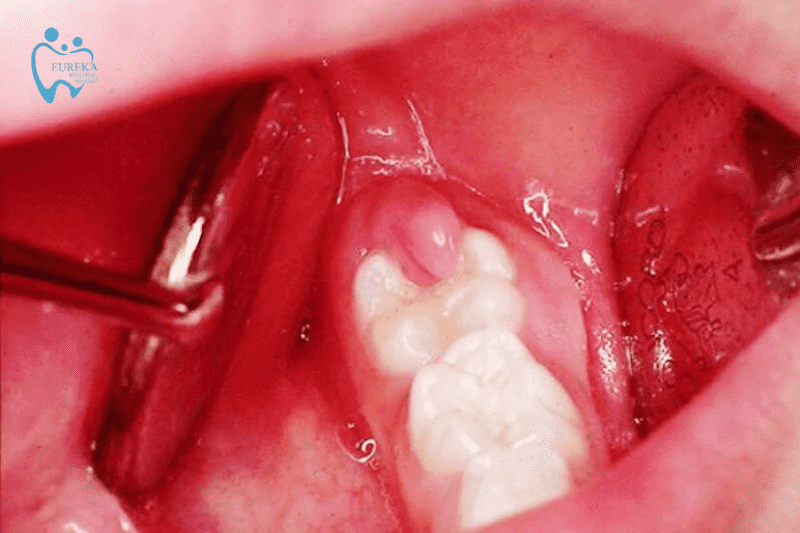

Dấu hiệu nhận biết viêm lợi trùm gần như giống với những dấu hiệu mọc răng khôn. Quan sát bằng mắt thường, cũng có thể phát hiện ra viêm lợi trùm.

- Phần lợi của người bệnh bị sưng phồng lên ở chính chỗ mọc răng khôn, có màu đỏ.

- Một số trường hợp lợi sẽ chảy dịch mủ ra khi ấn vào.